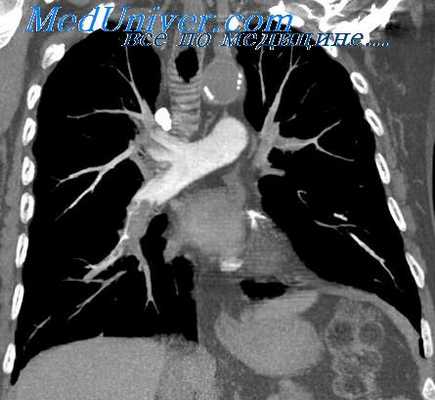

Контрастирование легочных и бронхиальных артерий с проведением серийных рентгенограмм на ангиографическом аппарате получило название ангиографии. Различают два вида ангиографии легочных артерий и их ветвей — общая (внутривенная) и избирательная (селективная) ангиопульмонография. При общей ангиопульмонографии контрастное вещество в количестве 50—60 мл вводят в локтевую вену.

Эта методика отмечается простотой, но имеет недостатки: нечеткое отражение мелких ветвей легочных артерий и необходимость большого количества контрастного вещества. Указанные недостатки устраняются при проведении селективной ангиопульмонографии. Расход контрастного вещества при ней в 5—6 раз меньше. Это связано с тем, что оно подводится непосредственно в легочную артерию или ее ветви через специальный зонд, вводимый через локтевую вену.

С помощью этой методики можно добиться подвода контрастного вещества вплоть до легочных капилляров. На таких селективных ангиограммах можно проследить все фазы кровообращения в исследуемом участке легкого: артериальную, капиллярную и венозную.

Ангиопульмонографию производят в специальной рентгенооперационной с использованием современной рентгеновской аппаратуры, обеспечивающей скоростную съемку с короткой экспозицией (0,003 с) и частотой 12 кадров и более в 1 с.